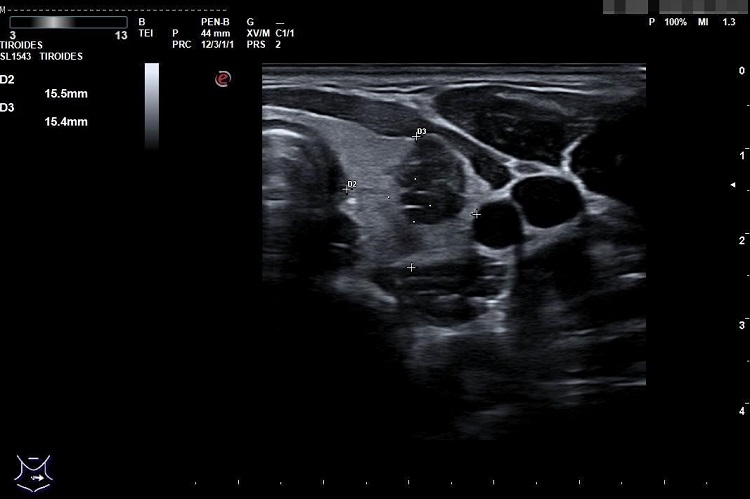

Presentamos el caso de una mujer de 16 años que consulta por aparición de bultoma doloroso compatible con adenopatía laterocervical tras infección de tracto respiratorio superior la semana previa. Durante el seguimiento se apreció aparición de nuevas adenopatías, por lo que se realizó ecografía tiroidea en su centro de salud, donde se observó tiroides con morfología normal y tamaño aumentado por la presencia en lóbulo tiroideo izquierdo de dos nódulos de consistencia sólida, fundamentalmente hipocogénicos, bordes lisos, circulación aumentada, con calcificaciones punteadas, que corresponden a un TIRADS 5 (Figura 1). Se realizó analítica que fue normal. Se derivó al Servicio de Endocrinología y se realizó eco PAAF, con hallazgo de carcinoma diferenciado de tiroides (variante papilar clásica) con metástasis ganglionares. Precisó tiroidectomía total y vaciamiento recurrencial junto con radioablación con rastreo.

Figura 1. Ecografía tiroidea. Nódulo en lóbulo tiroideo izquierdo, clasificación TIRADS 5